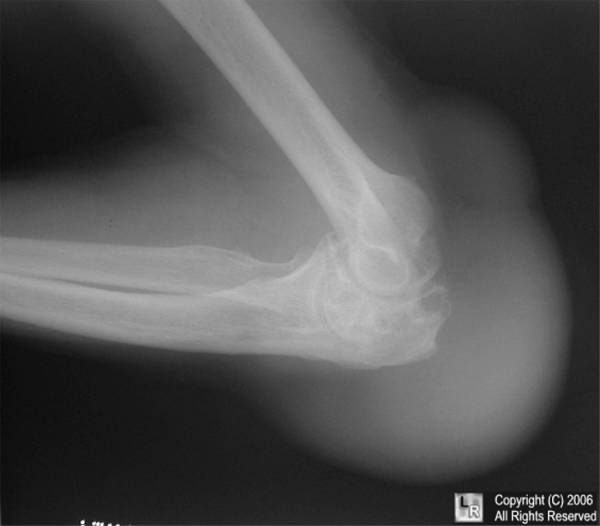

Розслабитися можуть власники «мікроскопічних» собак. Кишенькові чихуахуа та інші їм практично не хворіють. Зате великі породи, укупі зі своєю схильністю до захворювань серця і кровоносної системи, мають всі шанси почати шкандибати на трьох лапах вже до шести-семи років (а то й раніше). Взагалі, у ветеринарній практиці дуже часто зустрічається ситуація, коли доводиться, згнітивши серцем, присипляти лабрадорів, мастифів, кавказьких вівчарок і їм подібних собак, у яких просто відмовили задні лапи. Сумно, але факт. Найчастіше спостерігається ліктьовий бурсит: у собаки може бути вражена як одна, так і обидві лапи.

Які ж симптоми надійно вкажуть вам на необхідність терміново показати свого улюбленця ветеринарним лікарям? Як правило, хвороба розвивається дуже швидко. Тварина спершу невпевнено ставить лапу, потім починає відчутно кульгати (так починається бурсит ліктьового суглоба у собак). Поступово в районі ураженого суглоба утворюється опукла «блямбою», при промацуванні якої виразно відчувається наявність всередині якоїсь рідини. Якщо бурсит асептичний, то собака переносить цю процедуру спокійно, а ось при гнійному, гострому перебігу може взвизгивать від болю, а саме місце при цьому помітно набряклі і гаряче.